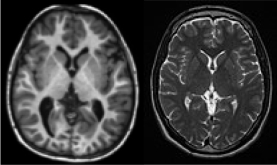

回波时间指的是180°脉冲产生至测量回波的时间,采用TE(echo time)表示。重复时间指的是两次90°脉冲之间的时间(脉冲序列是有周期性的),采用TR(repetition time)表示。通过调节TR、TE突出某个组织特征的影像被称作加权像(weighted image,WI)。我们在研究脑结构与功能时常见的加权像包括T1WI(T1-weighted imaging,基于T1加权成像)、T2WI,如图5.12所示。其中T1WI利用短重复时间(TR)和回波时间(TE)测量自旋晶格弛豫。不同的组织表现如表5.2所示,其中T2WI用长TR和TE时间测量自旋-自旋弛豫,更强的信号意味着更大的水分子含量。T1WI的TR常设置为100~500 ms,TE常设置为15~30 ms。T2WI的TR常设置为200~1 500 ms,TE常设置为90~150 ms。

图5.12 T1W I(左)、T2W I(右)